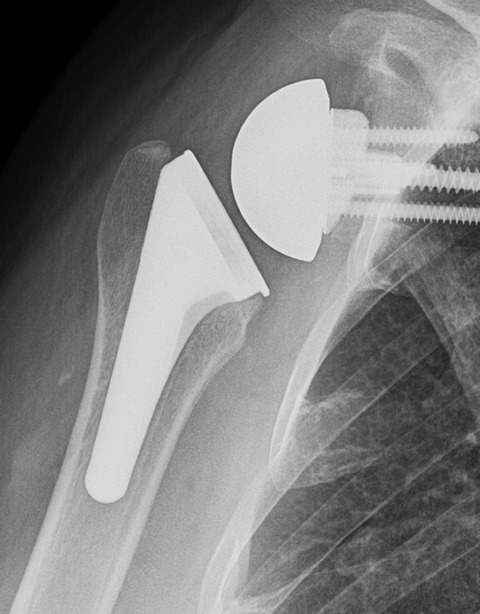

その仕組みを説明します。肩関節は本来、肩甲骨側に受け皿(関節窩[かんせつか])があり、上腕骨の先端にボール状の骨(上腕骨頭)が向かい合う「ボール&ソケット(受け皿)型」の構造をしています。このボールを腱板という筋建で受け皿に固定した状態で、三角筋という大きな筋肉で引き上げることで腕が挙がる仕組みです。一般的な人工肩関節(従来型人工肩関節置換術)では、この解剖学的な構造と同じ向きに人工関節を置き換えます。しかし、腱板が断裂して機能しない肩では従来型の人工関節を入れても、ボールの固定ができないままなので、腕を十分に挙げることができません.リバース型では人工関節の凸凹(ボールと受け皿)をあえて通常と逆に配置します。具体的には、肩甲骨側の関節窩にボール状の人工物をスクリュー固定します.このことでボールは腱板がないままでも既に固定されてしまったことになります.続いて、上腕骨側に受け皿の部品を取り付け、少し腕を下げた状態でボールと受け皿を組み合わせます。こうすることで、三角筋という、残っている大きな筋肉が引き伸ばされ、効率よく力が発揮できるようになります.このように人工物で関節の構造を反転させることで、腱板機能の肩代りを行い、残っている大きな筋肉である三角筋の力を増幅することで腕を挙げられるようになり、さらには可動部分は、神経のついていない人工物になるため、関節面のこすれによる痛みが生じにくくなります。

手術の方法について簡単に説明します。手術は全身麻酔で行い、肩の前方を切開して関節にアプローチします。傷んだ肩関節の骨や軟骨の一部を取り除き、そこに人工関節の部品を固定します。リバース型人工肩関節の人工部品は金属や医療用プラスチック(ポリエチレン)でできており、肩甲骨側にボール状の金属、上腕骨側にカップ状の部品をそれぞれしっかりと設置します。手術時間は肩の状態によって異なりますが、概ね2時間程度で終了します。出血量は通常200〜300ml程度で、輸血が必要になることはまれです。人工関節の設置後、必要な筋肉を修復し手術を終了します。